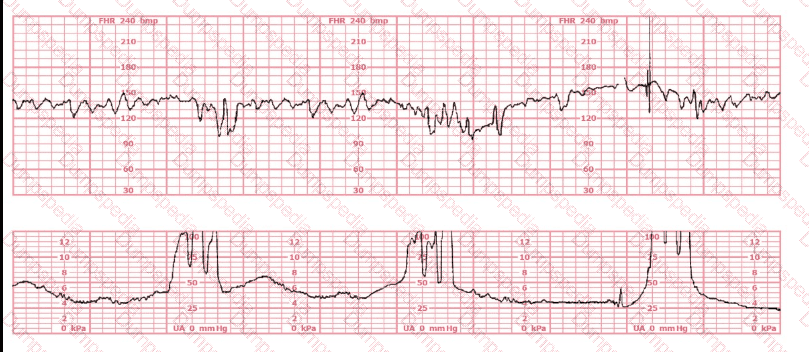

The tracing shown is from a woman at 28-weeks gestation in the post-anesthesia care unit (PACU) after an appendectomy. She is alert and awake. Based on this fetal heart rate pattern, the most appropriate intervention is: